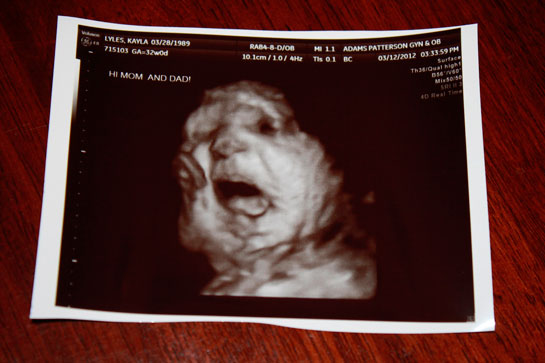

36 haftalık gebelik sürecinde yaşadıklarım gerçekten çok ilginç. Bebeğimin boyunun 47 cm ve ağırlığının 2 kg 700 gram olması beni heyecanlandırıyor. Her gün ortalama 30 gram alması da bu süreçteki gelişimini gösteriyor. Bebeğin doğuma hazırlandığını bilmek güzel ama bu haftayı atlatmanın verdiği rahatlıkla birlikte üzerimdeki yükün biraz hafiflemesi de sevindirici. Hormonal değişimler nedeniyle bedenimdeki gevşeme ve yumuşama beni yavaşlatıyor. Yürüyüşlerim değişti, bu da normal. Ancak bel ve pelvisteki ağrılar beni rahatsız ediyor. Yemek yeme konusunda da sıkıntılar yaşıyorum, bebeğim artık çok yer kaplıyor. Küçük porsiyonlarla beslenmek zorundayım. Mide yanmamın hafiflemesi, nefes almamı kolaylaştırdı ama bebeğim aşağı doğru inmeye çalıştıkça alt karın bölgesinde baskı hissediyorum, bu da rahatsız edici. Braxton Hicks kasılmalarının daha fazla hissedilmesi de dikkatimi çekiyor. Doğum sancılarının başlaması için her an hazırlıklı olmam gerektiğini biliyorum. Bebeğimin hareketlerinde azalma olursa ya da vajinal kanama yaşarsam hemen doktora gitmem gerektiğini unutmayacağım. Vajinal akıntıdaki artış beni endişelendiriyor ama cinsel birliktelikten sonra lekelenmenin normal olduğunu öğrenmek biraz olsun rahatlatıyor. Karın kaşıntım da dayanılmaz hale geldi; badem yağı ve E vitamini kremleri kullanmaya başladım. Uyku sorunlarıyla başa çıkmak için rahat kıyafetler giymek zorundayım. Ayaklarımda ve bileklerimdeki şişlik beni oldukça rahatsız ediyor fakat bol sıvı tüketmeye dikkat ediyorum. Halsizlik hissi normal ama doğumun yaklaşmasıyla birlikte bir enerji patlaması yaşıyorum. Artık tuvalet ihtiyacım da arttı, bu durum da yeni bir alışkanlık haline geldi. Tüm bu süreç gerçekten hem zorlu hem de heyecan verici!

36 haftalık gebelik sürecinin hem heyecan verici hem de zorlu yanlarını deneyimlemen gerçekten çok önemli. Bebeğinin gelişimiyle ilgili duyduğun sevgi ve mutluluk, bu sürecin en güzel yanlarından biri. 30 gramlık günlük kilo alımı, bebeğinin sağlıklı bir şekilde büyüdüğünün güzel bir göstergesi.